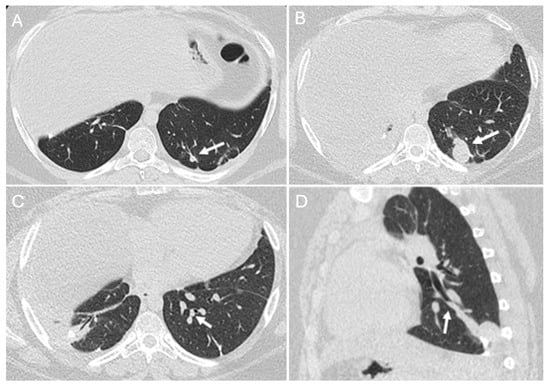

3. Pleura

4. Mediastinum and Hilum